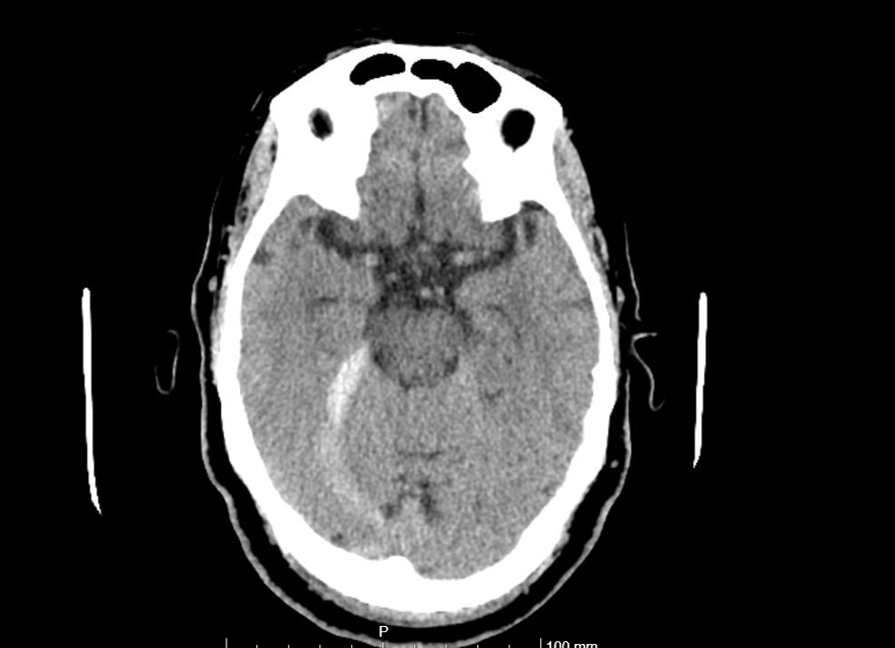

Pruebas de laboratorio normales. ECG con fibrilación auricular a 120 lpm. TAC craneal simple: Hemorragia subaracnoidea en tentorio derecho y hoz cerebral posterior junto con encefalopatía de pequeño vaso crónica severa (Fazekas 3).

Juicio clínico: Hemorragia subaracnoidea espontánea y otitis media crónica perforada en oído derecho.